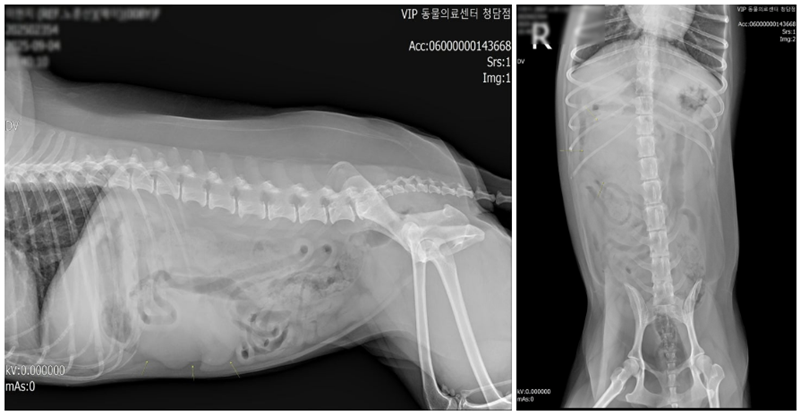

엑스레이 상 간 후방으로 연부조직 음영의 타원형 종괴가 확인되었습니다. 그 외 복강 내 특이소견은 없었습니다. ▼